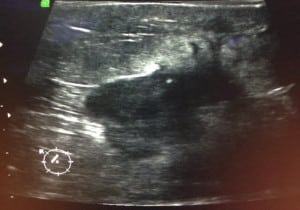

Caso 1.

((Mastografía digital: vemos en el tercio posterior un nódulo denso de márgenes espiculados, asociado a calcificaciones que varían en forma y densidad: relación a un cáncer ductal invasor))

((Imagen del mismo Nódulo por ultrasonido: se ve un nódulo sólido de márgenes angulados, altera el tejido que esta adyacente))